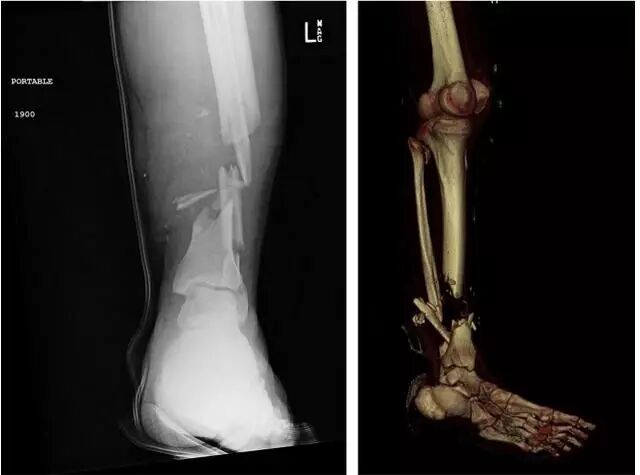

但是这位“硬汉”也有容易受伤的时候,例如骨折、骨肿瘤等,都会造成骨缺损。

骨头缺损,也就是两头的细胞之间出现了“鸿沟”,根据具体受伤部位的不同,“鸿沟”在3-5厘米以内的,细胞还能靠自己“跨”过去,然后慢慢重新长到一起;如果这个距离再大一点,细胞“跨”不过去了,就需要依靠一些辅助手段让它们“相遇”。

目前的辅助手段主要是填充。使用的填充物,有从患者自己身体里取出一些非承重部位的骨头,比如髂骨,也有从其他人体中取出的骨头,然后填充到缺失的部位。

不过,由于生物支架的硬度有限,而且还会按时降解,所以建议主要还是用于一些非承重部位的填充,比如人体上肢、躯干、手指等。如果要用在下肢等承重部位,还需要一些金属内固定物的辅助等。